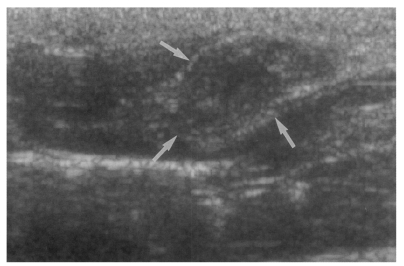

Sonography showed no dilatation of the bile duct confluence in the normal control group (Fig. 3). Sonograms showed moderate or marked dilatation of the bile duct confluence in the primary infection control group, the secondary infection control group, and the reinfection II group (Fig. 4, Table 2). A small number (1 of 7 in all groups) of animals showed mild dilatation of bile duct confluence in these groups (Fig. 5, Table 2). Dilated extrahepatic bile ducts were also observed. In the reinfection I group and the infection following immunization group, the degree of dilatation of the bile duct confluence was usually moderate (in n = 4 and n = 5, respectively). Marked dilatation was less frequent in these groups (n = 2 in each group).

Fig. 3

Sonogram of a rat in the normal control group without C. sinensis infection, showing no dilatation of the bile duct confluence.

kjp-42-7-g003.jpg